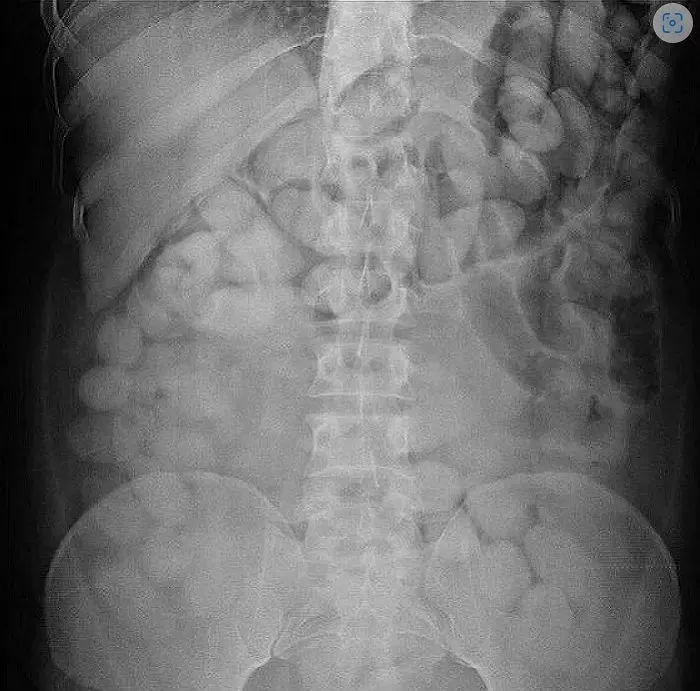

한편 A씨의 소식이 주목을 받으면서 공항에서 마약이 적발된 외국인의 충격적인 X-ray 사진이 재조명되고 있다.

태국 매체 치앙마이 뉴스 등에 따르면 사건은 6월 태국 푸껫 국제공항에서 발생했다. 이날 남아프리카공화국 국적 20대 남성의 뱃속에서 코카인이 든 소형 비닐봉지 115개가 발견됐다.

당시 세관 당국은 그의 행동이 수상해 짐을 뒤지는 등 수색을 벌였지만 불법적인 물건을 발견하지 못했다. 의구심을 풀지 못한 당국은 병원으로 보내 엑스레이 촬영을 시도했고 몸 속에 원형 물체가 가득찬 것을 확인했다.

병원에서 꺼낸 남성의 몸에 있던 수상한 물체들은 코카인을 싼 작은 비닐봉지였다.

개수는 무려 115개로 전체 무게는 1.49kg, 시가로는 447만 밧(한화 약 1억 6000만원)치였다.